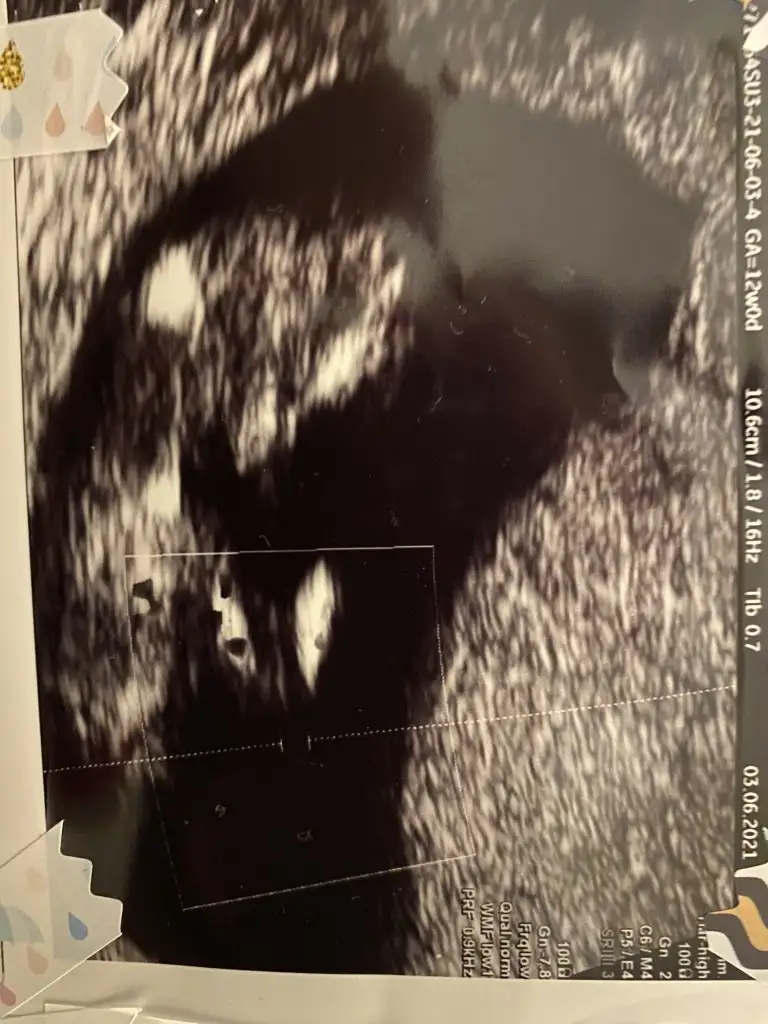

Merhabalar bizimde bebeğimiz 12 haftalarda yorumlarsanız çok sevinirim Ikra meyra Ikra meyra

12 Mayıs'ta kalp atışını duyduğum gün, karından, şimdi 10 haftayız.

Tahmin rica etsem ??